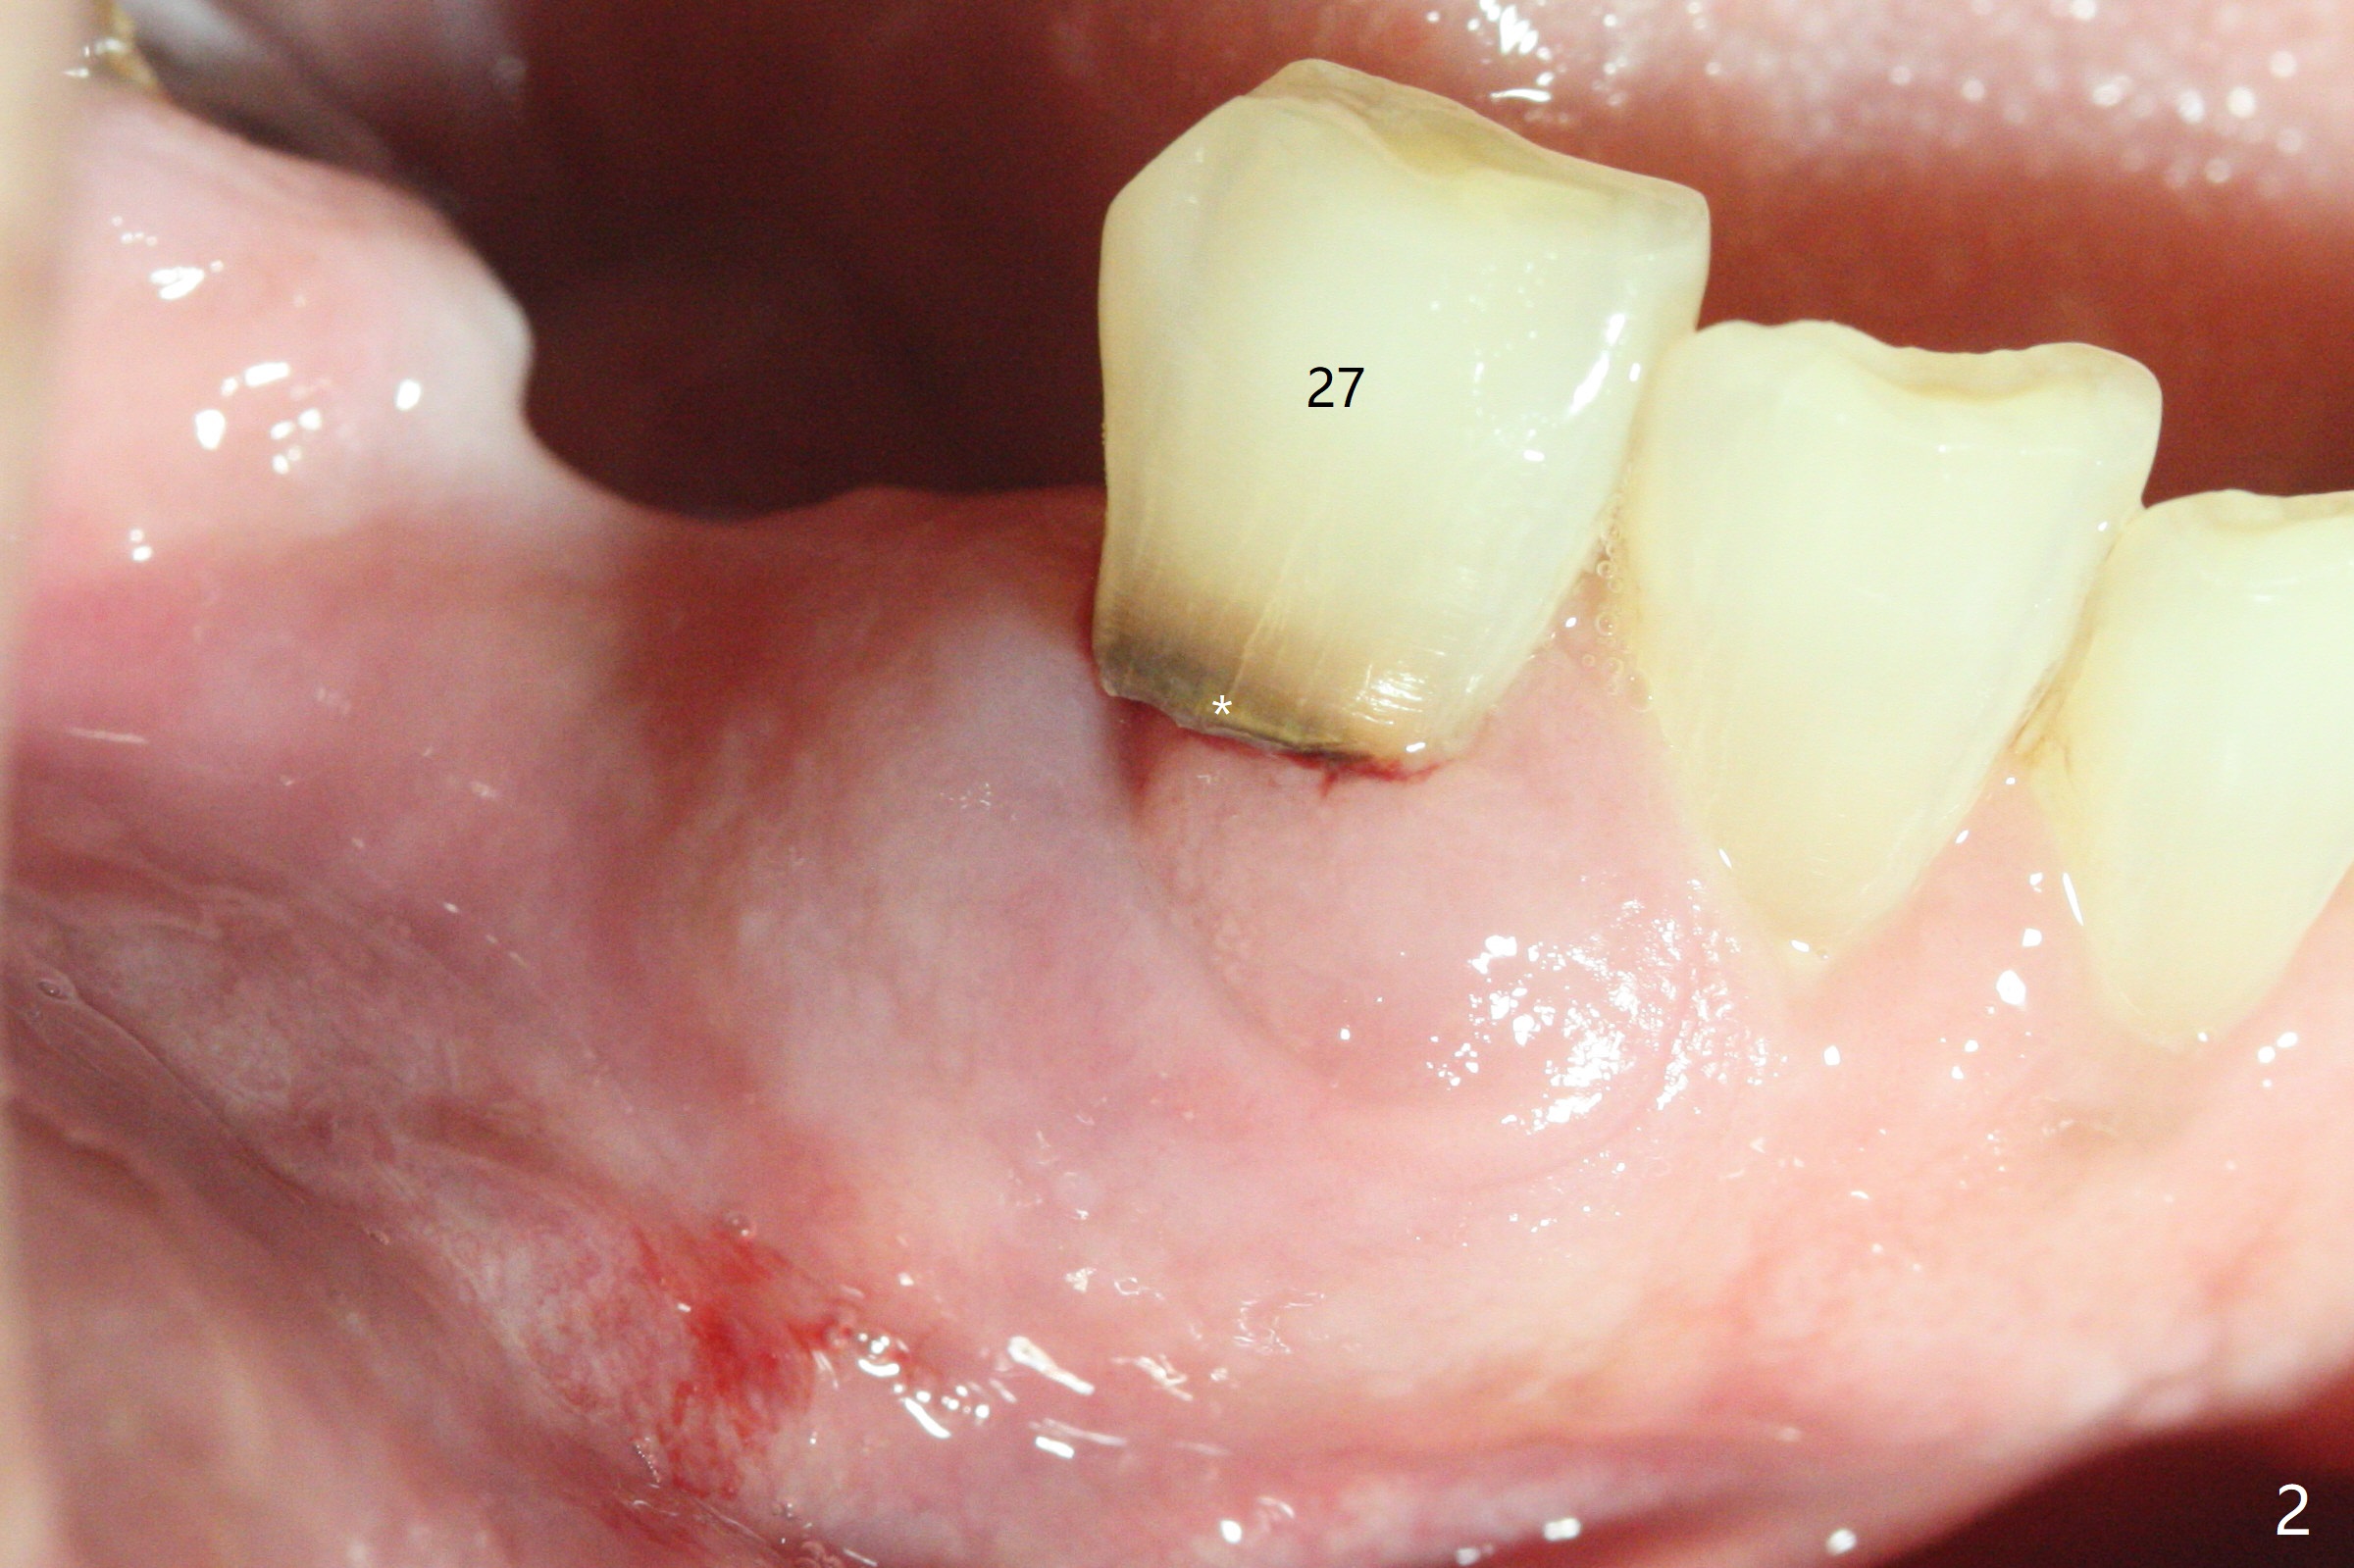

A 63-year-old man requests repair of Class V caries at #27 (Fig.1,2 *). With local anesthesia, Diode laser is used for gingivectomy for composite (Fig.3 C).